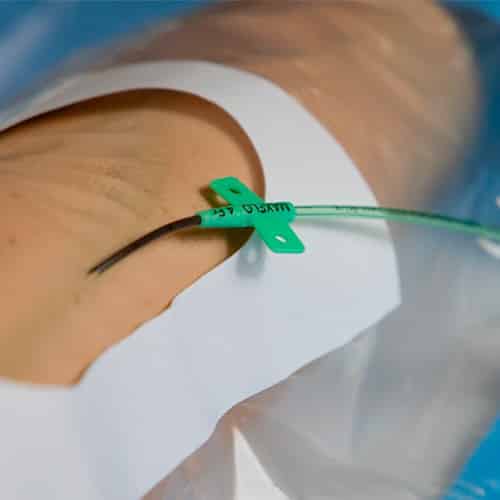

Es un acceso vascular que se usa en pacientes que requieren tratamientos >6 días con el fin de evitar los múltiples pinchazos y reducir las complicaciones debidas a las limitaciones de los catéteres cortos.

Se inserta en venas profundas del brazo (basílica, braquiales o cefálica) mediante técnica ecoguiada y su punta se ubica en el tramo axilo-subclavia.

Entre sus ventajas:

- Al alcanzar venas de diámetros importantes disminuye las complicaciones (flebitis, extravasación)

- Su material, el Poliuretano permite tratamientos de 1 mes o más

- Técnica poco invasiva

- Un catéter para todo el tratamiento

Video explicativo en el que se ve de forma práctica cómo insertar un catéter de línea media mediante la técnica Seldinger sin dilatación (Seldinger pura)

Técnica de inserción Seldinger pura